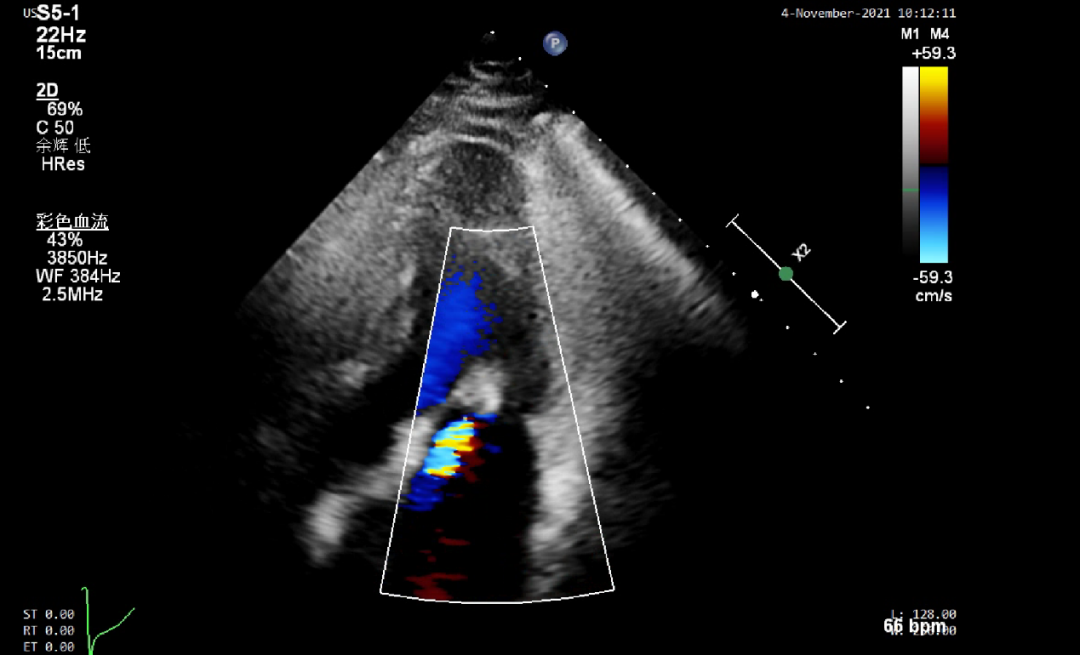

手术于全麻下进行,手术采用经股静脉穿刺房间隔途径,将导管鞘系统送入患者左心房,到达二尖瓣口,全程在TEE引导下,术者通过评估二尖瓣反流位置、瓣叶脱垂位置以及反流程度等,精准夹合二尖瓣叶,患者一准确植入一枚二尖瓣夹,瓣膜夹位置稳定,植入后反流基本消失(图3),耗时两个半小时,二尖瓣跨瓣平均压力阶差1mmHg,左心房平均压力即刻从28mmHg降到10mmHg,患者二较患者一难度稍大,但在术者娴熟的操作中手术更加顺畅,依然一枚二尖瓣钳夹完成,二尖瓣跨瓣平均压力阶差1mmHg,左心房平均压力即刻从27mmHg降到7mmHg,瓣膜夹位置稳定,植入后反流基本消失(图4),耗时两小时,两位患者术后均恢复良好,三、四天后遂出院。

图4 患者二,反流完全消失